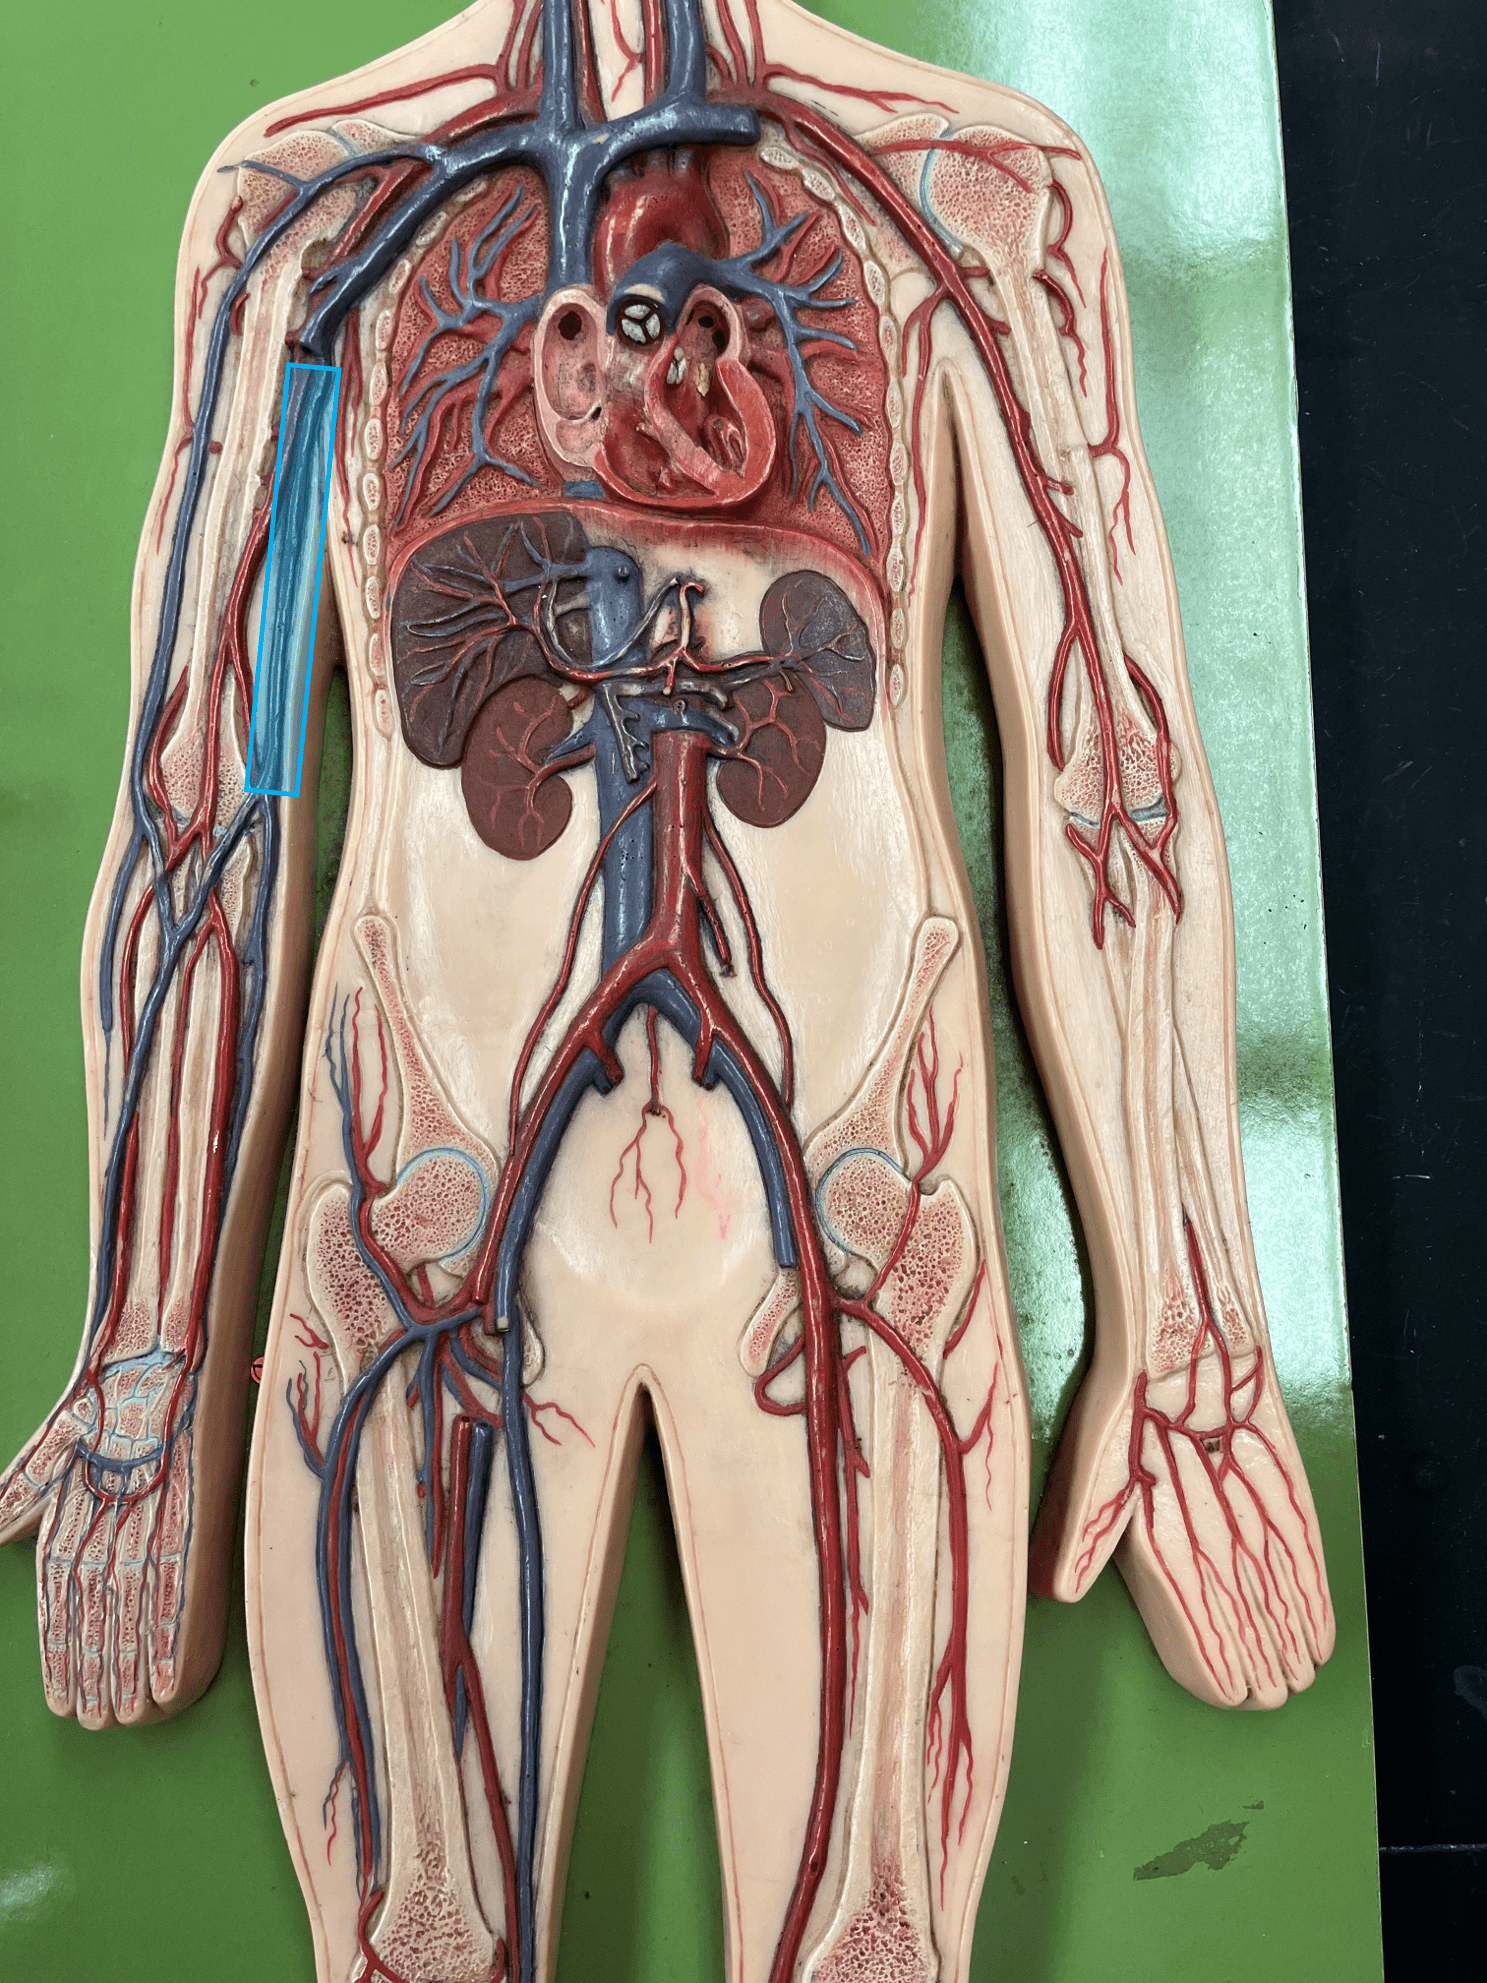

• Consists of an inner endothelium and an outer basement membrane.

• Also known as the tunica intima.